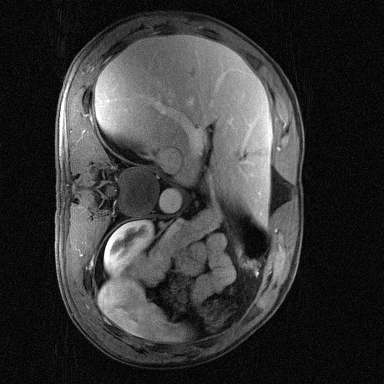

Supervised Deep-Learning (DL)-based reconstruction algorithms have shown state-of-the-art results for highly-undersampled dynamic Magnetic Resonance Imaging (MRI) reconstruction. However, the requirement of excessive high-quality ground-truth data hinders their applications due to the generalization problem. Recently, Implicit Neural Representation (INR) has appeared as a powerful DL-based tool for solving the inverse problem by characterizing the attributes of a signal as a continuous function of corresponding coordinates in an unsupervised manner. In this work, we proposed an INR-based method to improve dynamic MRI reconstruction from highly undersampled k-space data, which only takes spatiotemporal coordinates as inputs. Specifically, the proposed INR represents the dynamic MRI images as an implicit function and encodes them into neural networks. The weights of the network are learned from sparsely-acquired (k, t)-space data itself only, without external training datasets or prior images. Benefiting from the strong implicit continuity regularization of INR together with explicit regularization for low-rankness and sparsity, our proposed method outperforms the compared scan-specific methods at various acceleration factors. E.g., experiments on retrospective cardiac cine datasets show an improvement of 5.5 ~ 7.1 dB in PSNR for extremely high accelerations (up to 41.6-fold). The high-quality and inner continuity of the images provided by INR has great potential to further improve the spatiotemporal resolution of dynamic MRI, without the need of any training data.